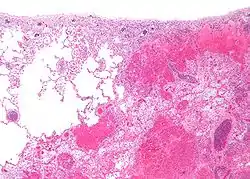

![]() صورة مجهرية لاحتشاء رئوي (يمين الصورة) وبجانبة نسيج رئوي طبيعي سليم (يسار الصورة). صورة مجهرية لاحتشاء رئوي (يمين الصورة) وبجانبة نسيج رئوي طبيعي سليم (يسار الصورة). | |

تنقسم الاحتشاءات إلى نوعين وفقاً لكمية النزف:

- احتشاء أبيض تؤثر على الأجهزة الصلبة مثل القلب، الطحال، والكلى فانسدادها في معظم الأحيان يكون ناتج عن تجمع الصفائح الدهنية في جدران الاوعية الدموية، وبذلك تصبح الأجهزة بيضاء.

- احتشاء أحمر، وتؤثر عموماً على الرئتين. يحدث فيه انسداد وتتألف المنطقة المتموتة من خلايا الدم الحمراء والليفين.